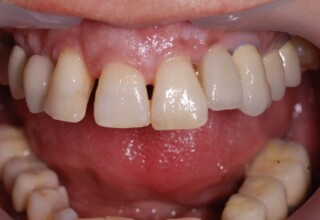

Composite Resin Veneers

Resin veneers are an inexpensive mode of esthetic improvement of anterior teeth, premolars also. Their potential is admirable and their limit is the operator’s clinical dexterity and imagination. In this case there were multiple problems with the upper four incisors: staining, poor inclinations, diastemas, multishading, poor interrelationship and poor tooth-gingiva ratios. They were restored with four direct composite resin veneers (one on a porcelain implant crown!) which were manufactured intraorally!!!